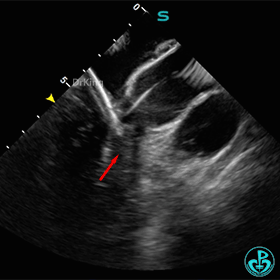

封堵器完全释放后位置、形态观察

封堵器完全释放后盘面平整,呈“工”字型骑跨于室间隔两侧,未见瓣膜影响。